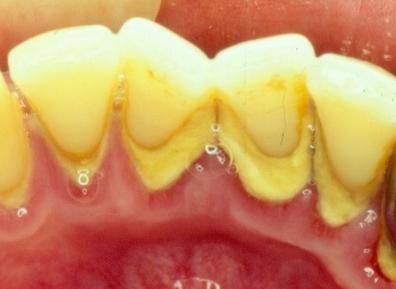

1,患牙周围的软组织面临感染发炎、萎缩溃烂的风险。因为牙结石会不断积累从而向患齿的龈下发展,这样会对患齿周围的牙周组织不断形成刺激,很容易导致其被细菌感染,从而引发炎症,牙周炎等就是这么来的。

如果是因为出现牙石而形成了牙周袋,会更容易使得细菌和食物残渣积累,造成更大范围的破坏。严重的甚至会导致牙周溃烂,牙龈出血等问题。

2,患齿下的骨质组织也会受到影响。牙结石经过钙化后会变得坚硬,如果任由其不断发展,侵犯到患齿的龈下,就会与牙槽骨发生对抗,这样会使得牙龈因受到一个外力从而出现向内萎缩,一旦萎缩过度,可能就会造成患齿的松动和脱落。